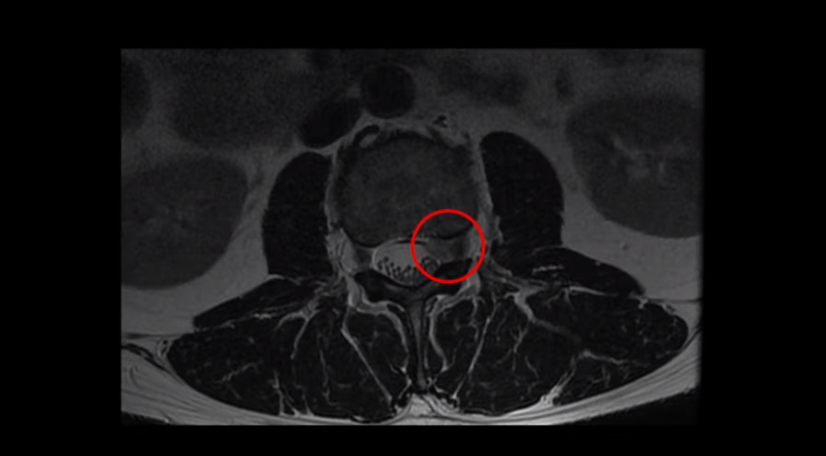

우선 이분 MRI를 보면 디스크가 심하게 터져 위로 밀려 올라가 있습니다. 신경가지가 나가는 구멍을 보시다시피 막고 있으니까 마비 증상과 방사통이 있습니다.

그런데 저희 모커리는 이렇게 심하게 파열된, 특히 수핵이 밀려 나와서 아래로 흘러내리거나 위로 올라가 버릴 정도의 심한 파열일수록 오히려 치료가 더 쉽고 잘 된다고 여러 영상을 통해 지속적으로 말씀드리고 있습니다. 그 이유는 디스크 파열이 심하면 심할수록 밀려 나온 수핵이 깨끗이 흡수되어 없어질 가능성이 높기 때문입니다. 그럼 이분은 치료가 끝나고 6개월 후에 MRI를 다시 찍으셨는데 과연 밀려 나온 디스크 수핵이 전부 다 깨끗이 흡수되었을까요? 이분이 치료 끝나고 6개월 후에 찍은 MRI 영상은 치료 후 결과영상에서 보실 수 있습니다.